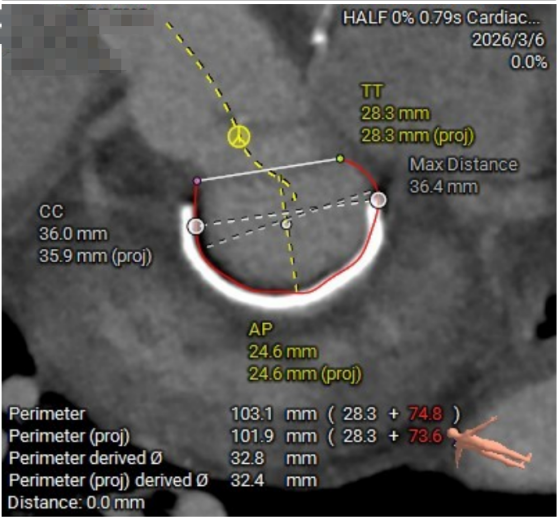

二尖瓣瓣环测量

03.jpg

04.jpg